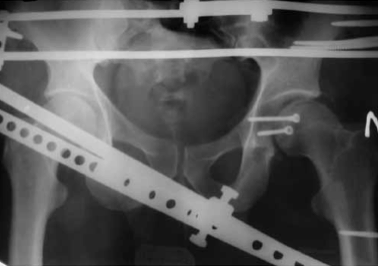

Для ранней активизации больного операция заканчивается установкой аппарата внешней фиксации. Аппарат позволяет гарантированно стабилизировать тазобедренный сустав с заданной или регулируемой разгрузкой, что создает условия не только для срастания перелома, но и для расправления или восполнения участков импрессии или компрессии с восстановлением структуры субхондрального слоя (рис. 2, 3).

Обзорная рентгенограмма таза. Состояние после открытой репозиции и фиксации верхнего отдела заднего края вертлужной впадины винтом. Стабилизация и разгрузка тазобедренного сустава в аппарате внешней фиксации

Рентгенография тазобедренного сустава в двух проекциях (прямая и аксиальная). Срок после оперативного лечения — 6 лет